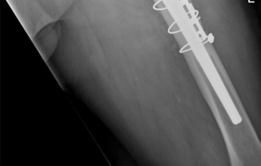

Reconstruction techniques : Acetabulum— augment buttress, morcellized bone grafting, porous tantalum shell. Femur—modular revision stem, trochanteric plate, cerclage cables (Figs. 19.20 and 19.21).

16. Trochanteric osteotomy repaired using a plate, cerclage cables, and allograft strut.

4. Femur—since the patient had a long-stem cemented femoral component, we elected to perform an extended trochanteric osteotomy to gain access to the cement mantle and to aid in the extraction of the femoral component. We also elected to use a trochanteric plate with several cerclage cables and an allograft strut to augment stability for the revision femoral component. A modular femoral revision component that gave primary diaphyseal fixation was chosen due to severe proximal femoral bone loss secondary to osteolysis.

7. #### Postoperative Radiographs

(Figs. 19.20 and 19.21)